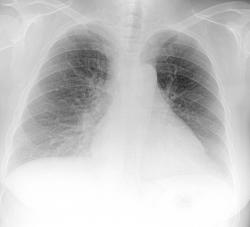

Добрый день коллеги! Сегодня проглядывал снимочки легких, по просьбе своей коллеги, с целью исключения метастазов и увидел  представленную картину. Пациентка 50 лет, лежит  в стационаре с диагнозом: Злокачественное новообразование яичника? Мts в надключичные лимфатические узлы. Мысли сразу про лимфогенные метастазы,  поглядел сразу в архиве ФЛГ от 11.08.09г. два первых снимка, два последних сегоднишним днем. Ваше мнение?

Два последних снимочка это сегоднишние цыфровые рентгенограммы, КТ-у нас пока вышло из строя. По УЗИ находят образование в почке и яичнике.

Я бы не рискнул "увидеть" на представленных Вами снимках лимфогенные метастазы (не смотря на анамнез). На мой взгляд, динамика по снимкам несущественна, да и та связана с застойными изменениями в легких. А на фоне застоя лимфогенные метастазы по рентгенограмме отдифференцировать очень трудно.

В том то и дело уважаемый Alex застойные изменения в МКК, минимальные, а картина похожа на лимфастаз.

Ну что-же, Вам на месте виднее. Тогда хотя бы срединную томограмму попробуйте сделать, лучше корни рассмотрите, да и лимфоузлы средостения при лимфогенном метастазировании поражаются чаще, чем не поражаются.